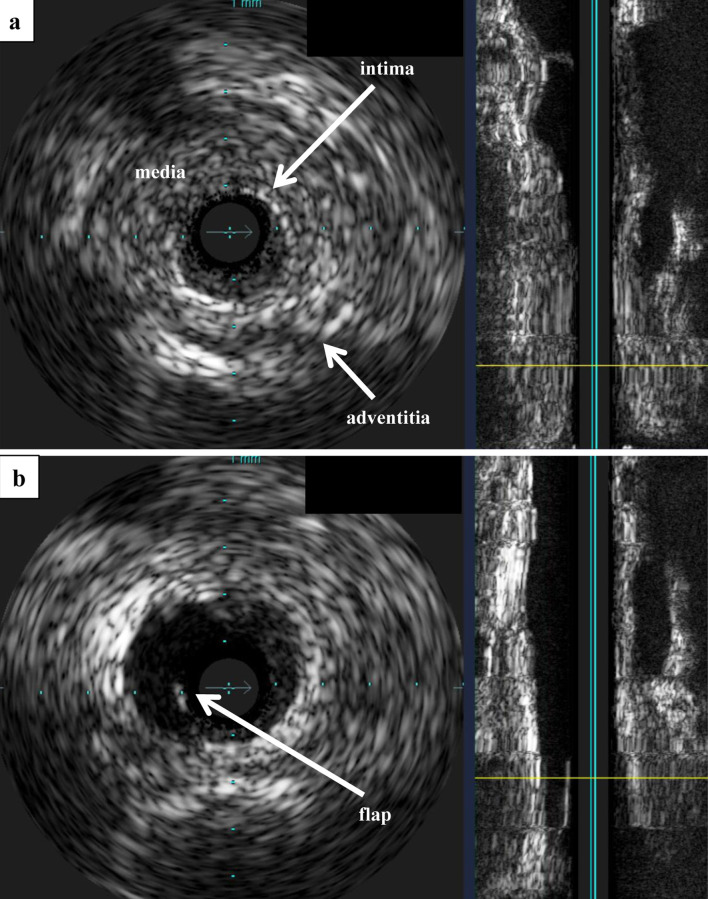

Renovascular hypertension (RVHT) is most commonly caused by renal artery stenosis (RAS) secondary to arteriosclerosis. Other causes of RVHT include fibromuscular dysplasia (FMD) and other rare causes, such as Takayasu arteritis (TA). A male patient in his early 20s presented with hypertension. Laboratory findings were positive for hypokalemia as well as elevations in plasma renin activity and aldosterone concentration. Plain computed tomography revealed atrophy of the right kidney, and magnetic resonance angiography revealed right RAS. A diagnosis of RVHT was suspected, and he was admitted to the cardiovascular ward. After percutaneous transluminal renal angioplasty (PTRA) to treat the right RAS, a typical course was observed with decreased blood pressure, normalizing hypokalemia, and decreased plasma renin activity and aldosterone concentration (which previously were extremely elevated). As angiography showed no remarkable arteriosclerosis of other vessels and given the patient's young age, FMD was suspected as the underlying cause of RVHT. However, the angiographic findings of RAS in the proximal renal artery and the lack of "string-of-beads" appearance were atypical for FMD. The patient had chronic inflammation, and further investigation revealed severe stenosis of the right carotid artery. The high C-reactive protein value and the thickened aortic wall in the computed tomography were the suggestive signs for TA. The patient was diagnosed with TA and started on steroid therapy. Although moderate stenosis remained after revascularization of the renal artery in this patient, hypertension improved markedly, demonstrating the effectiveness of PTRA. Given the diagnosis of TA as the underlying disease, the likelihood of recurrent RVHT due to restenosis of the renal artery remains high, and strict follow-up is thus required.